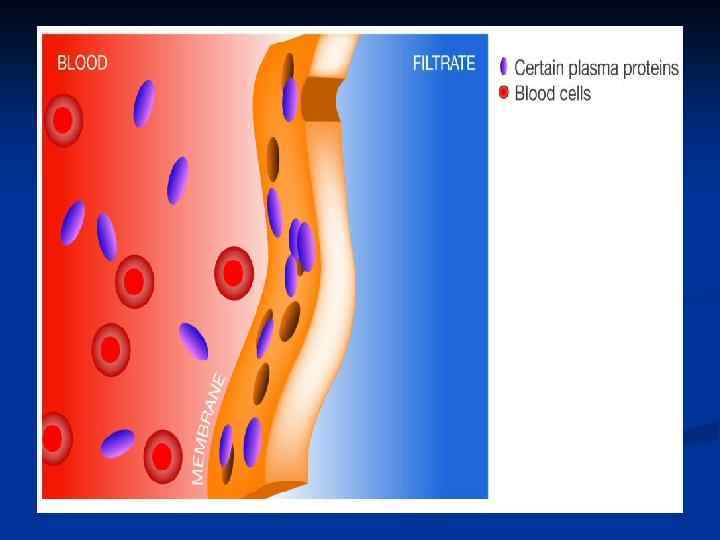

n Гемосорбцияны қандағы әр түрлі зиянды заттардан тазарту үшін қолданады. Ағзада әдетте бұл бауырдың жұмысы. «Гемо» -қан, «сорбция» -ағзаны уландырушы зиянды заттардан тазарту, яғни қанды, қан сары суын, лимфаны токсиндерден, улы заттардан тазарту үшін сорбентпен толтырылған арнаулы түтік арқылы сүзгіден өткізілуі.